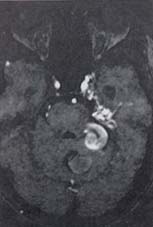

Otras lesiones como malformaciones vasculares arteriovenosas y/o aneurismas gigantes pueden ser causa de su alteración (Figuras 16 y 17).

Figura 16.Extensa malformación arterio-venosa con un componente dural proyectado

a la cisterna pontocerebelosa.

Figura 17. Aneurisma gigante vertebro-basilar izquierdo parcialmente trombosado con efecto

de masa sobre el contenido cisternal pontocerebeloso.